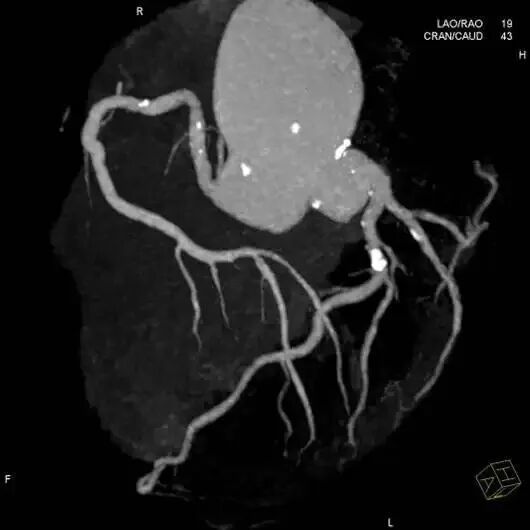

3)冠状动脉CT血管造影(CTA)

冠脉CTA是冠状动脉CT的血管成像的简称,也就是在静脉注入造影剂,然后通过CT扫描重建出这个冠状动脉血管的一种检查的方法,相比较诊断冠心病的金标准冠状动脉造影来说,是一种无创检查,更适合于高危人群的心血管疾病筛查。